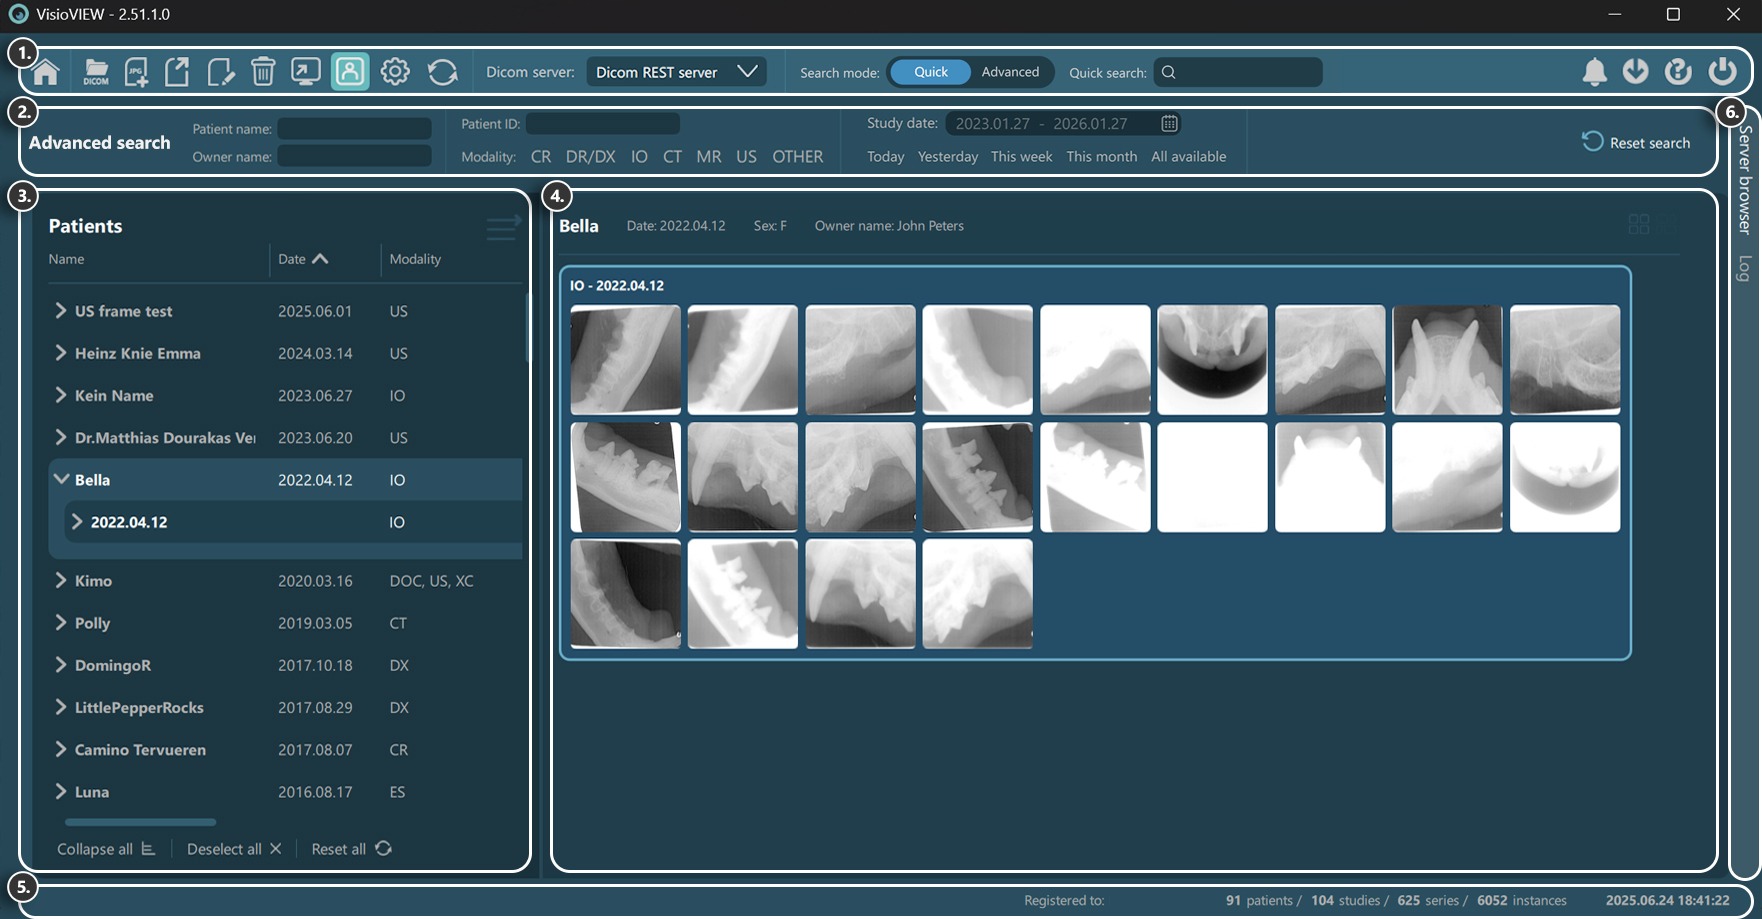

The Study Browser consists of several sections, each serving a specific purpose. Below is a detailed description of each section.

Browser Toolbar¶

Home screen

Upload DICOM files to PACS server

Import and convert images to DICOM files

Export selected studies

Edit main DICOM tags of selected studies

Delete selected studies

Open selected studies

Toggle Patient mode

Global VisioVIEW settings

Refresh server data

Select configured servers

Toggle between Quick and Advanced search mode

Quick search

Notifications

Image transfers

Help

Quit the software

Advanced Search¶

Filter studies by patient name / owner name

Filter studies by patient ID

Filter studies by modality type

Filter studies by date interval

Reset all active filters

Study List¶

Preview Pane / Home Screen¶

Patient information

Download selected studies’ image data (optional)

Thumbnail image aspect ratio (unified/original)

Study preview

Information Bar¶

Current active background task information

Licensing information

Study Browser data information

Date & time of last server synchronization

Study Browser/Log¶

Freely switch between the Study Browser or the software logs by choosing the appropriate tab.